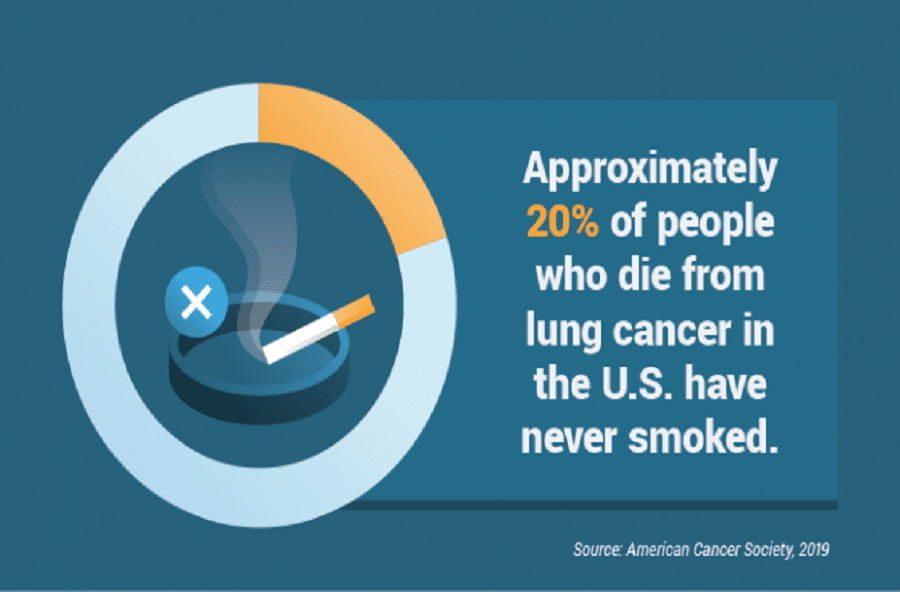

Εθνικό Ινστιτούτο Υγείας: Ο καρκίνος του πνεύμονα κατηγορείται για την κύρια αιτία θανάτων που σχετίζονται με τον καρκίνο σε όλον τον κόσμοΣύμφωνα με τα Εθνικά Ινστιτούτα Υγείας, οι ερευνητές εντόπισαν τρεις υποτύπους καρκίνου του πνεύμονα μεταξύ των ατόμων που δεν κάπνισαν ποτέ, οι οποίοι αποτελούν περίπου το 10-20% του πληθυσμού των ασθενών με καρκίνο του πνεύμονα. Οι όγκοι μη καπνιστών βρέθηκαν να προέρχονται από μεταλλάξεις που οφείλονται σε φυσικές σωματικές διεργασίες, ανακοίνωσε η υπηρεσία.